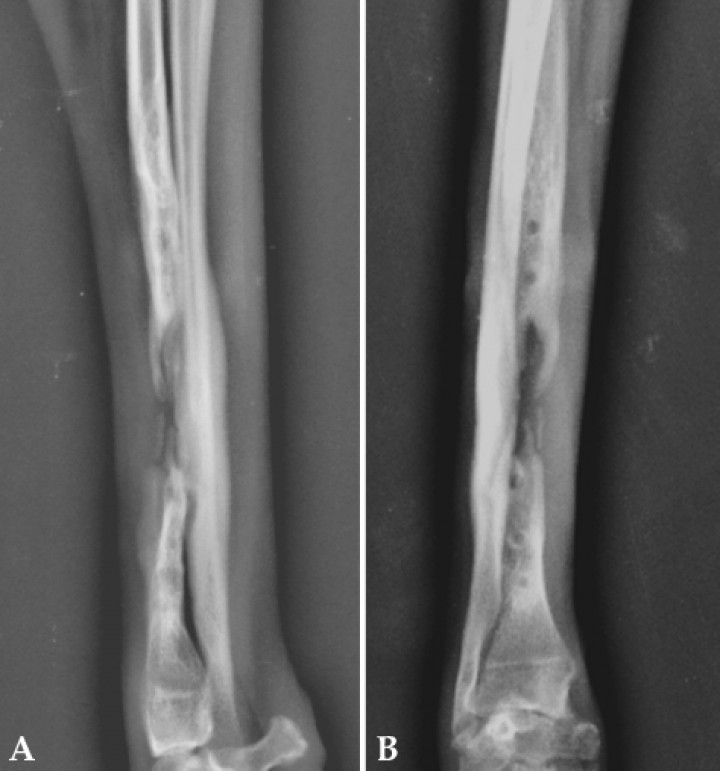

Se repitió el mismo tratamiento 3 veces más con un intervalo de 10-12 días entre cada una de las sesiones empleando los mismos parámetros, durante las cuales se fue observando una mayor tolerancia del paciente. A partir de la segunda sesión el paciente comenzó a cargar peso con la extremidad tratada, acudiendo a la tercera sesión con una cojera de 1/5. En la cuarta sesión se retiró definitivamente el vendaje. Durante el periodo de terapia con ondas de choque se fueron realizando radiografías de control (Fig. 3), en las que se apreciaron zonas de neoformación ósea activa a partir de los extremos del defecto del radio. En esta fase introdujimos la cinesiterapia pasiva de las articulaciones ahora expuestas (carporradial, intercarpiana, carpometacarpiana, metacarpofalángica e interfalángicas) y la cinesiterapia activa, comenzando con ejercicios sencillos como inicios de cargas, balanceos, cargas alternas, etc.

<p>(<strong>A</strong>) Radiografía mediolateral. (<strong>B</strong>) Radiografía craneocaudal. Se observan claros indicios de neoformación ósea en ambos fragmentos proximal y distal (aproximadamente 1 mes después de comenzar el tratamiento con ondas de choque, día 210).</p>

(A) Radiografía mediolateral. (B) Radiografía craneocaudal. Se observan claros indicios de neoformación ósea en ambos fragmentos proximal y distal (aproximadamente 1 mes después de comenzar el tratamiento con ondas de choque, día 210).